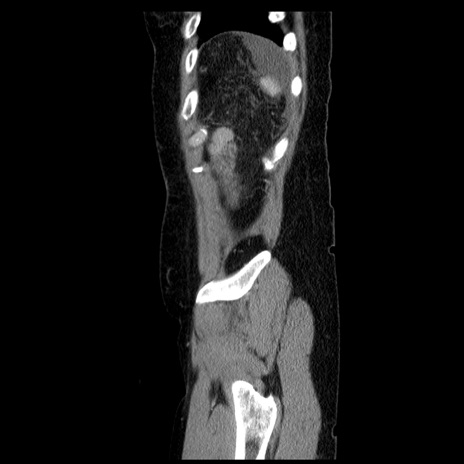

症例6(矢状断像)

【症例】50歳代女性

【主訴】下腹部痛

【現病歴】本日朝より下痢2回あり。 昼食を食べた後、嘔吐3回、下腹部痛認め、症状軽快せず、当院救急搬送。

最終食事:本日昼(生ものなし)。 昨日の夜、刺身を食ぺたとのこと。周囲に同様の症状の者なし。普段、排便は毎日あるとのこと。

【既往歴】卵巣癌術後(8年前に当院で卵巣摘出)

【身体所見】 意識清明、腹部:平坦、腸蠕動音→、やや硬、下腹部自発痛・圧痛あり、反跳痛あり、筋性防御なし。

【データ】WBC 16000、CRP 0.01